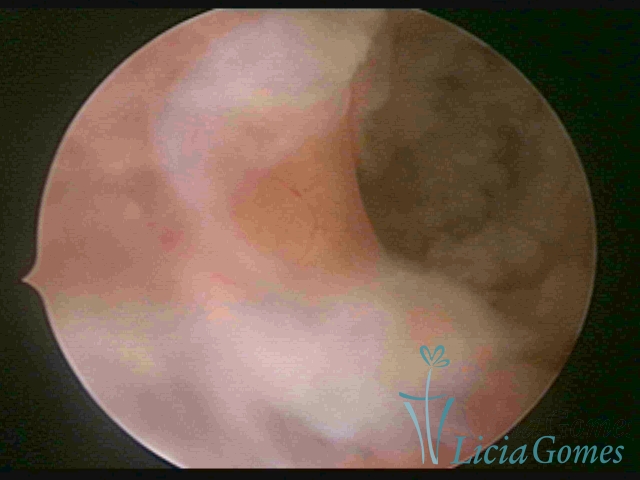

SINÉQUIA TIPO MUCOSA